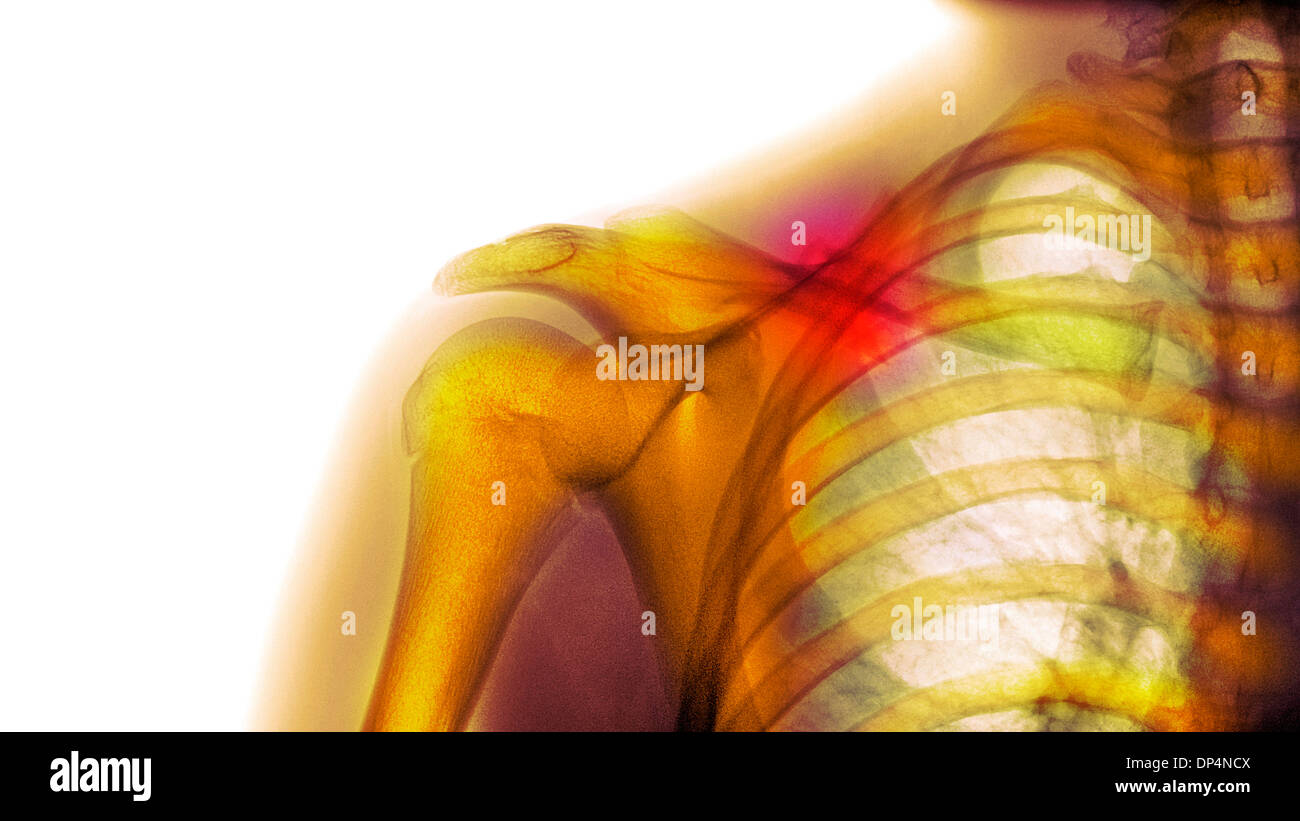

Collarbone X Ray . the clavicle (collarbone) is one of the most fractured bones in the body. To learn more about the. The ap clavicle is often indicated in patients with suspected clavicular injuries following trauma such as falling onto ones side. To help pinpoint the location of the fracture; The posterior shoulder should be in contact with image receptor (ir) or tabletop, without rotation of body. The standard ap view of the clavicle is taken with the patient upright or sitting, with arms at the sides, chin raised, and looking straight ahead. imaging of the clavicle. Symptoms of a broken collarbone include severe pain and swelling at the site of the fracture and with visible deformity in some cases. It can be requested as part of a. the radiographic series of the clavicle is utilized in emergency departments to assess the clavicle, acromioclavicular and.

the clavicle (collarbone) is one of the most fractured bones in the body. To learn more about the. The ap clavicle is often indicated in patients with suspected clavicular injuries following trauma such as falling onto ones side. To help pinpoint the location of the fracture; Symptoms of a broken collarbone include severe pain and swelling at the site of the fracture and with visible deformity in some cases. The posterior shoulder should be in contact with image receptor (ir) or tabletop, without rotation of body. It can be requested as part of a. imaging of the clavicle. The standard ap view of the clavicle is taken with the patient upright or sitting, with arms at the sides, chin raised, and looking straight ahead. the radiographic series of the clavicle is utilized in emergency departments to assess the clavicle, acromioclavicular and.

Broken collarbone or clavicle fracture signs, symptoms and treatment